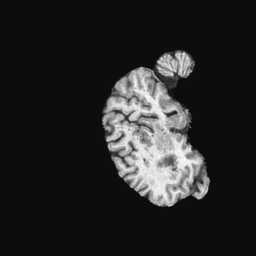

Exp. 2: Fetal brain data is used to test the robustness of our approach under real conditions. Fetuses younger than 30 weeks very often move a lot during examination. Fast MRI sequences allow artifact free acquisition of individual slices but motion between slices corrupts consistent 3D information. Fig. 3 shows that our method is able to accurately predict also under these conditions. For this experiment we use from three orthogonally overlapping stacks of ssFSE slices covering the fetal brain with approximately 20-30 slices each. We are ignoring the stack transformations relative to the scanner and treat each individually. For , 28 clinically approved motion compensated brain reconstructions are resampled into a volume with spacing. A density of 500 unique sampling normals has been chosen via the Fibonacci sphere sampling method with 25 sampling planes evenly spaced between -25 to +25 on the Z-axis. This gives a plane spacing of 2mm, sampling only the middle portion of the fetal brain. Training took approximately 10hrs for 30 epochs. Prediction, i.e., the forward pass through the network, takes approx. 12 ms/slice.

Slices, from a motion corrupted MRI stack, are segmented and cropped. Since there is no ground truth for the queried images, an arbitrary fetal atlas is used for visualization in Fig. 11 and 12.